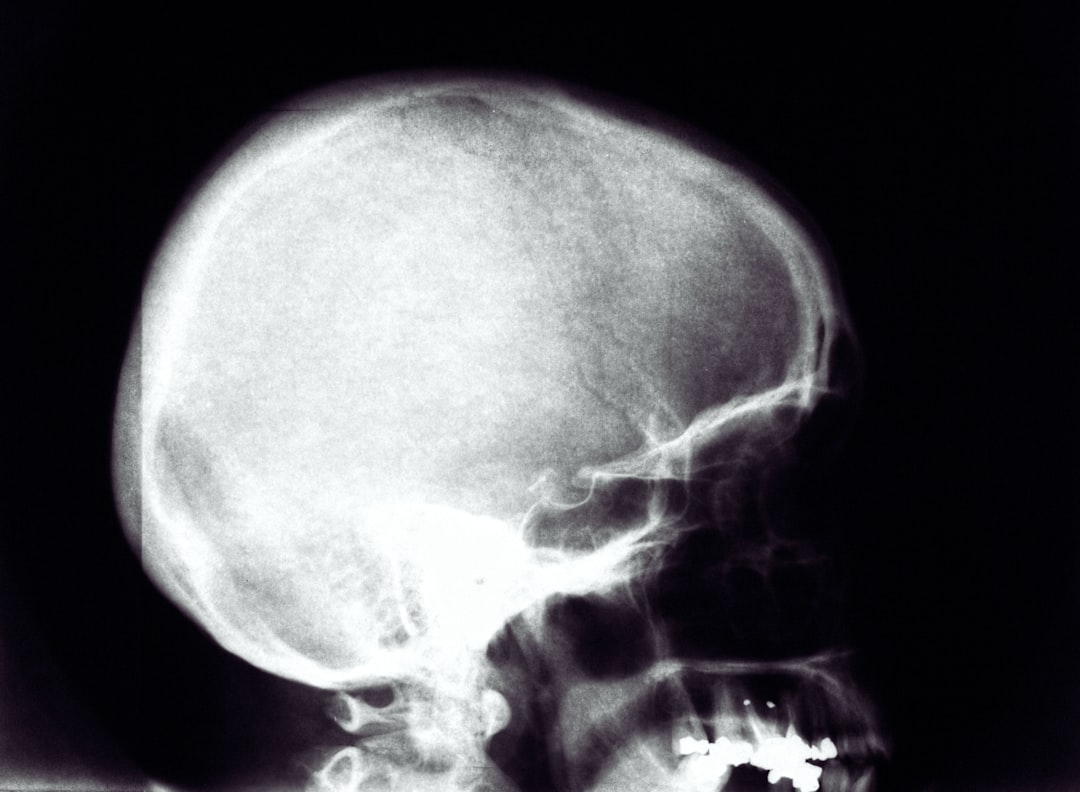

Consultarea unui medic devine esențială atunci când presiunea în cap devine persistentă sau severă. Dacă această senzație este însoțită de alte simptome alarmante precum confuzie mentală, dificultăți de vorbire sau slăbiciune într-o parte a corpului, este crucial să căutăm asistență medicală imediată. Aceste simptome pot indica afecțiuni grave precum accidente vasculare cerebrale sau alte probleme neurologice.

De asemenea, dacă presiunea în cap interferează semnificativ cu activitățile zilnice sau nu răspunde la tratamentele obișnuite (cum ar fi analgezicele), este recomandat să discutăm cu un specialist pentru a identifica cauzele subiacente ale acesteia. Un medic va putea efectua evaluări adecvate și va recomanda tratamente personalizate pentru a gestiona simptomele.